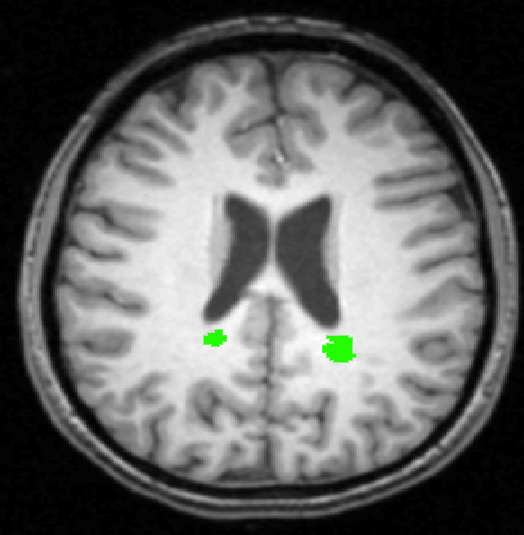

We use images from three different studies (see Fig. 1 for examples of slices):

10 MS patients from the MS Lesion Challenge [11] scanned at the Children’s Hospital of Boston (CHB), scanned with T1, T2 and FLAIR at 0.50.50.5mm resolution.

2.

- 3.

Here again the differences between study populations influence the class priors. On average, the percentage of voxels that are lesions are 1.6%, 2.6% and 0.2% in CHB, RSS and UNC respectively. The differences between subjects also vary: these are relatively small for CHB and UNC, but very large for RSS. In RSS, the subject with the least lesion voxels has only 0.08%, while the patient with the most lesion voxels has 14.3%.

In all experiments, we use 10,000 voxels per image for training the classifiers, and 50,000 voxels per image for evaluating the classifiers. For BT, we sample these voxels randomly within the brain mask. For WML, we use only a subset of the voxels within the brain mask, following [2]. Because WML appear bright on FLAIR images, we train and test only on voxels within the brain mask with a normalized FLAIR intensity above 0.75. Out of this subset, we sample the voxels in two ways. For training and evaluating the classifiers, we oversample the WML class, such that WML voxels are 10 times more likely to be sampled than non-WML voxels. For calculating the distances at test time when target labels are not available, the voxels are sampled randomly.